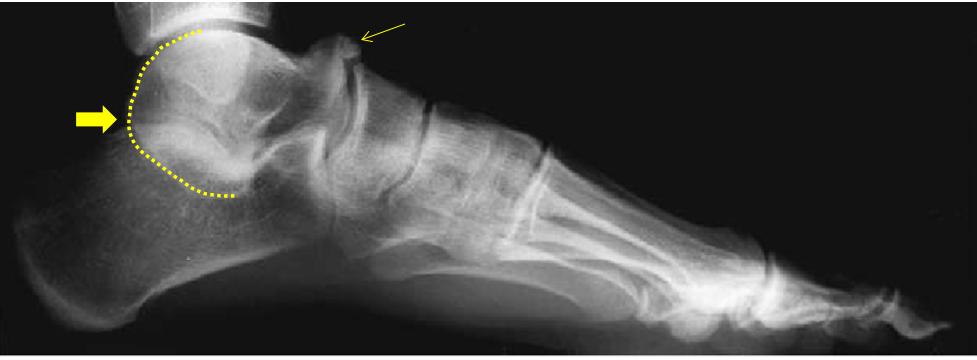

图 | 黄色箭头指向跟距骨桥

大多数跟距骨桥没有临床症状(75%)。 疼痛多因扭伤或是长时间运动劳累后引发 。

足负重侧位可见距骨上方喙突样骨赘,距下后关节面形态异常,中关节面消失征,C型征。

图 | 跟距骨桥的X线表现